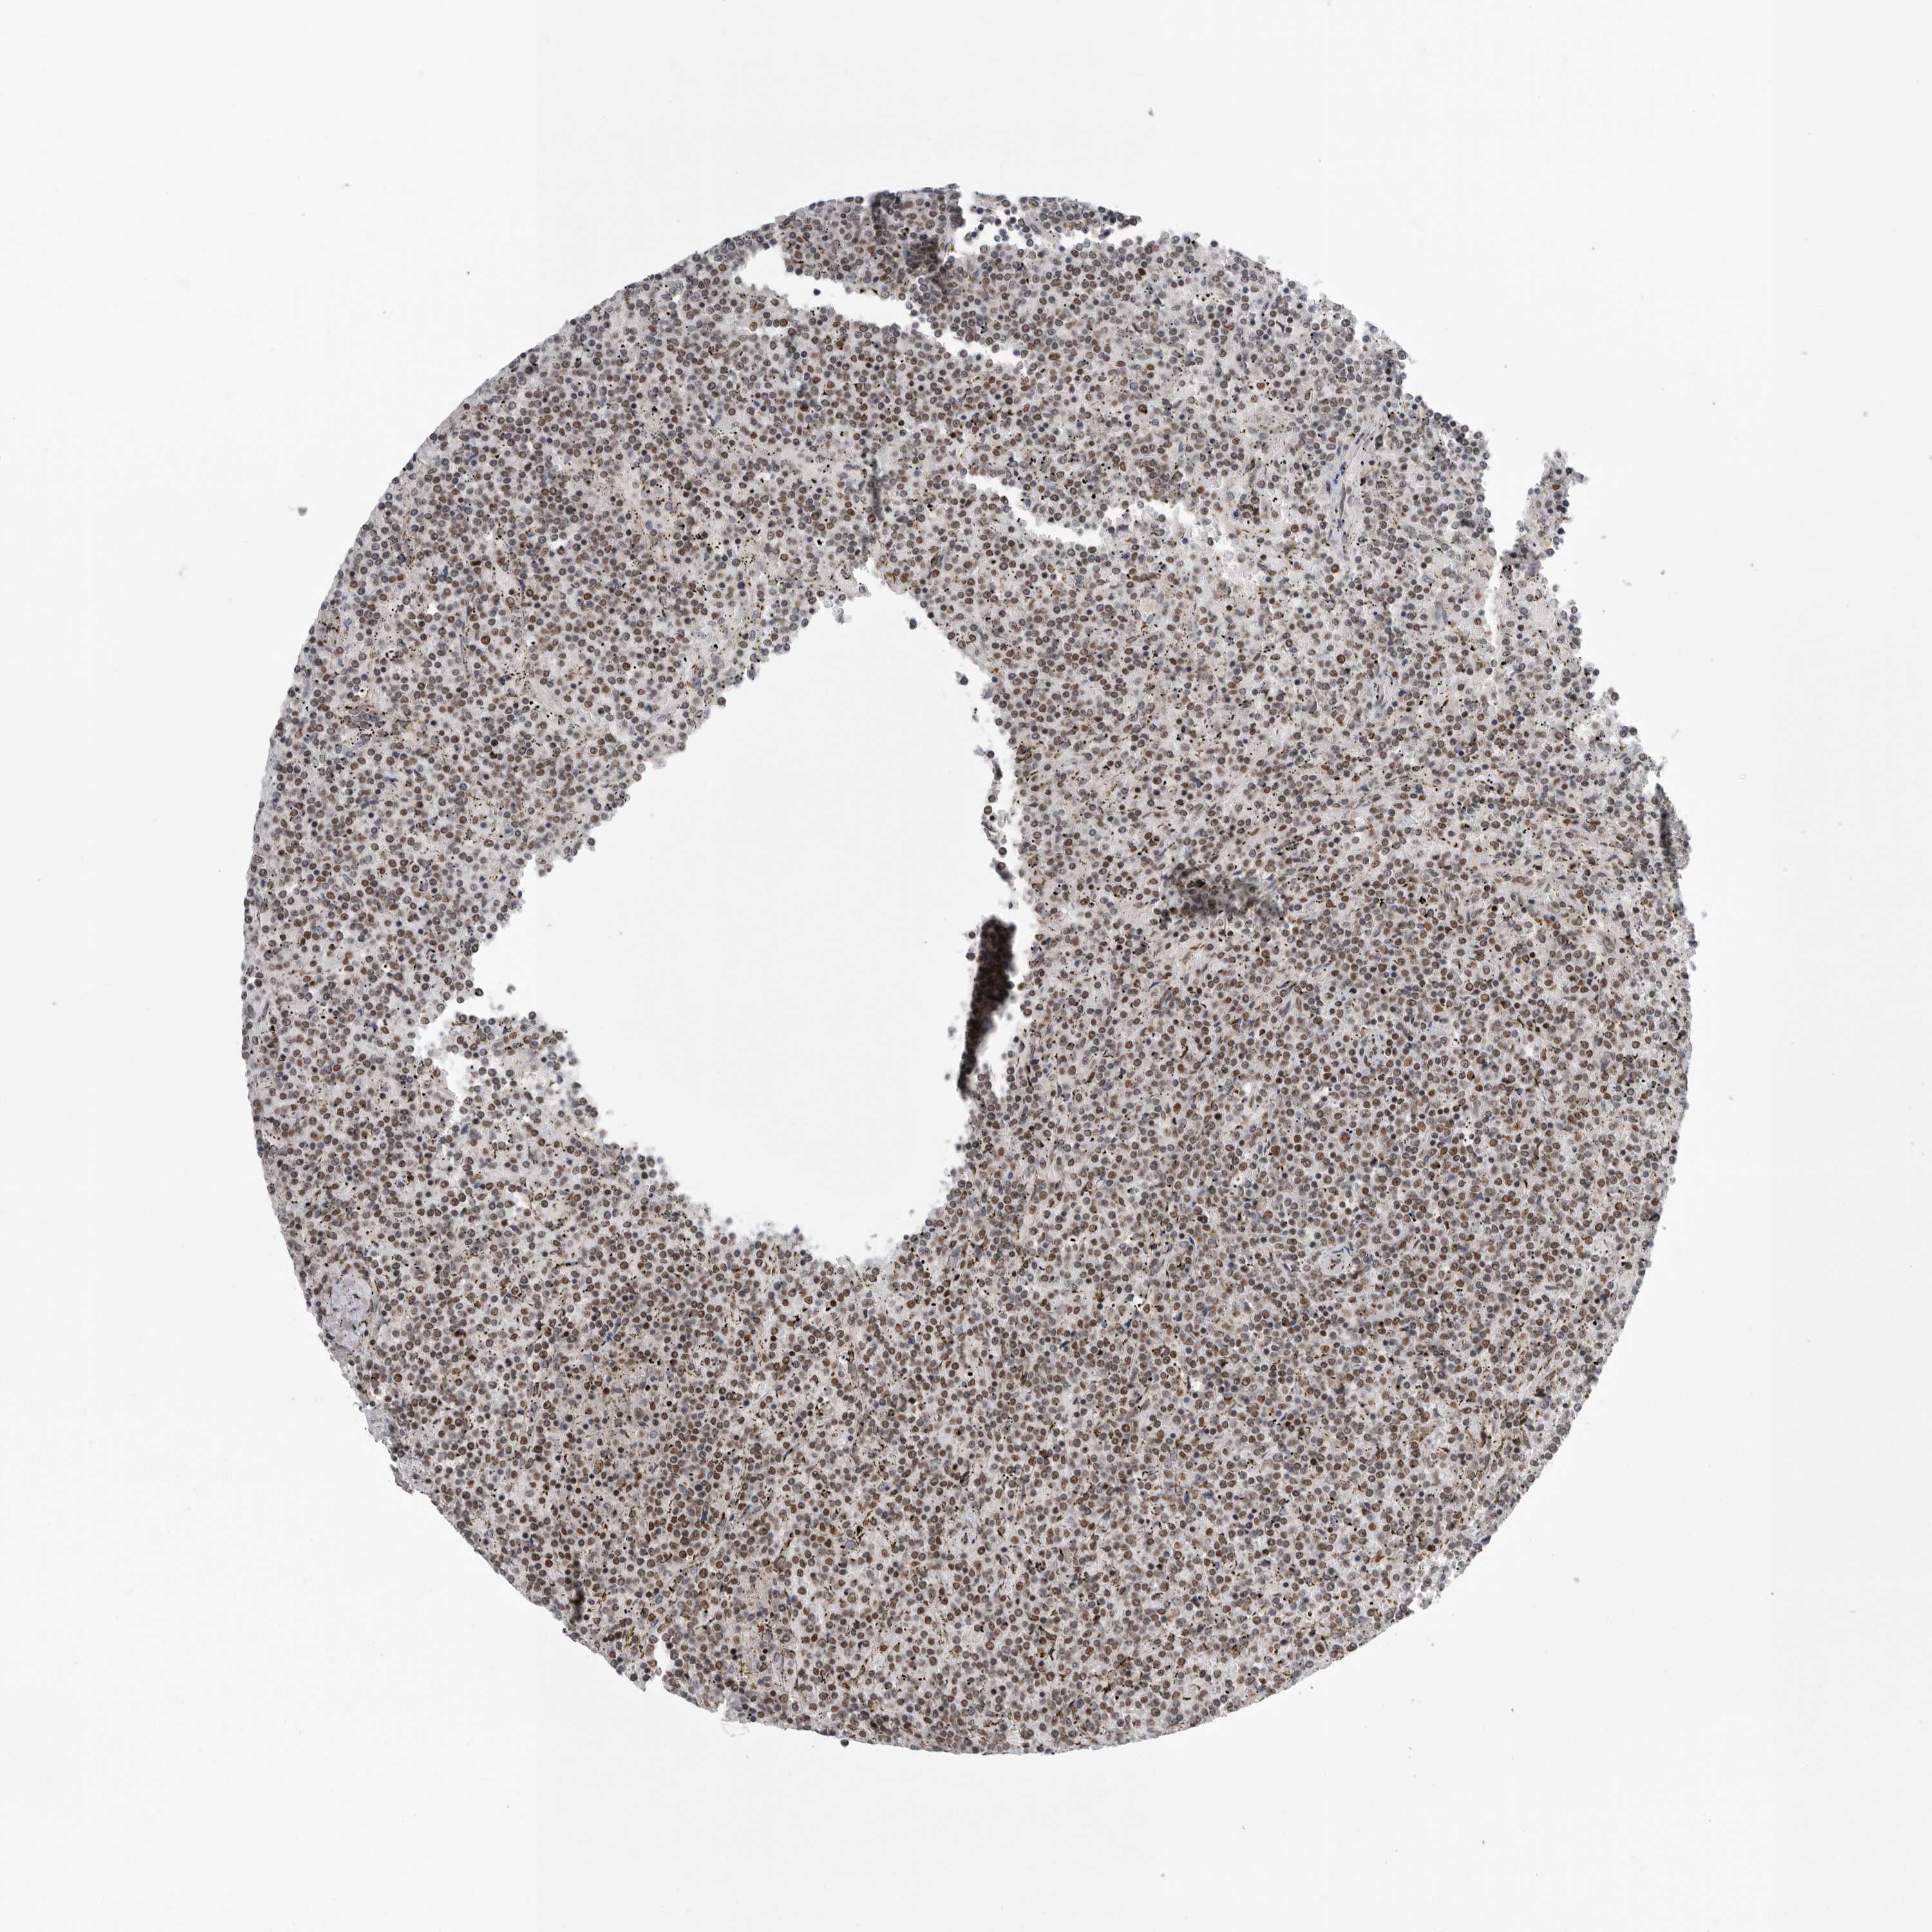

CANCER LYMPHOMA Show tissue menu

LYMPHOMA - Protein expressioni

A mouse-over function shows sample information and annotation data. Click on an image to view it in a full screen mode. Samples can be filtered based on level of antibody staining by selecting one or several of the following categories: high, medium, low and not detected. The assay and annotation is described here.

Each image is clickable and will lead to virtual microscopy that enables deeper exploration of all samples and also displays staining intensity scores, fraction scores and subcellular localization as well as patient and tissue information for each sample.

Antibody CAB025600

Antibody CAB026380

Antibody CAB079773

Staining

High

Medium

Low

Not detected

Intensity

Strong

Moderate

Weak

Negative

Quantity

>75%

75%-25%

<25%

None

Location

Nuclear

Cytoplasmic/membranous

Cytoplasmic/membranous,nuclear

Hodgkin's disease, NOS

Malignant lymphoma, non-Hodgkin's type, Low grade

Malignant lymphoma, non-Hodgkin's type, High grade